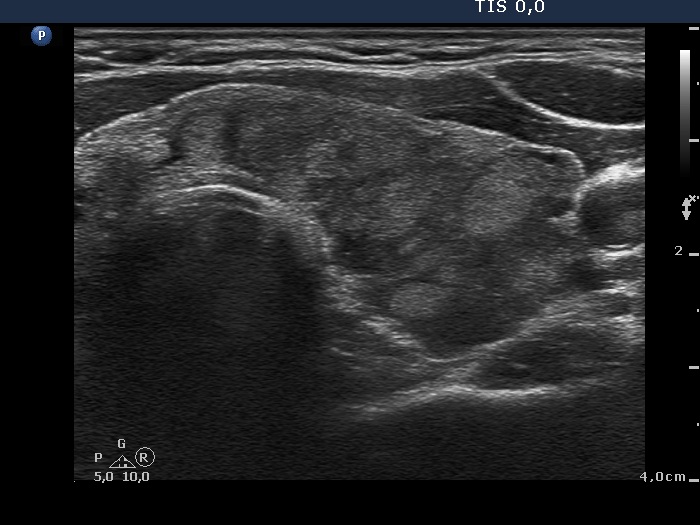

The borders of the nodule - case 880 (ultrasonographic picture 5)

Right lobe, longitudinal scan